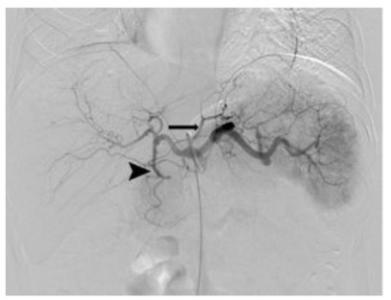

L’embolisation bariatrique permet la perte de poids, mais comment ? L’embolisation gastrique ou bariatrique, une procédure moins invasive, qui consiste à injecter des billes microscopiques sous contrôle d'imagerie dans l'artère alimentant l’estomac en sang. Les perles bloquent le flux sanguin et réduisent la production de ghréline, l’hormone qui stimule la faim. De premières études montré l’efficacité de l’embolisation pour la perte de poids, mais, comme le souligne ici l’auteur principal, le Dr Edwin A. Takahashi, radiologue vasculaire à la Mayo Clinic : « Il n’existe aucune donnée sur ce qui contribue à la perte de poids, que les patients perdent ou non de la graisse, ou encore de la masse musculaire, ou enfin une combinaison des deux ».

16 patients en surpoids ou obèses ayant subi une embolisation de l'artère gastrique gauche pour traiter un saignement gastro-intestinal ont subi une tomodensitométrie permettant à l’équipe de mesurer leur composition corporelle. Ces examens ont été effectués avant et environ 1,5 mois après la procédure. Les résultats ont été comparés à ceux d'un groupe témoin de 16 patients ambulatoires n'ayant pas subi d'embolisation de l'artère gastrique gauche, mais ayant subi un scanner à deux périodes différentes pour des douleurs abdominales non spécifiques. L’analyse montre que :